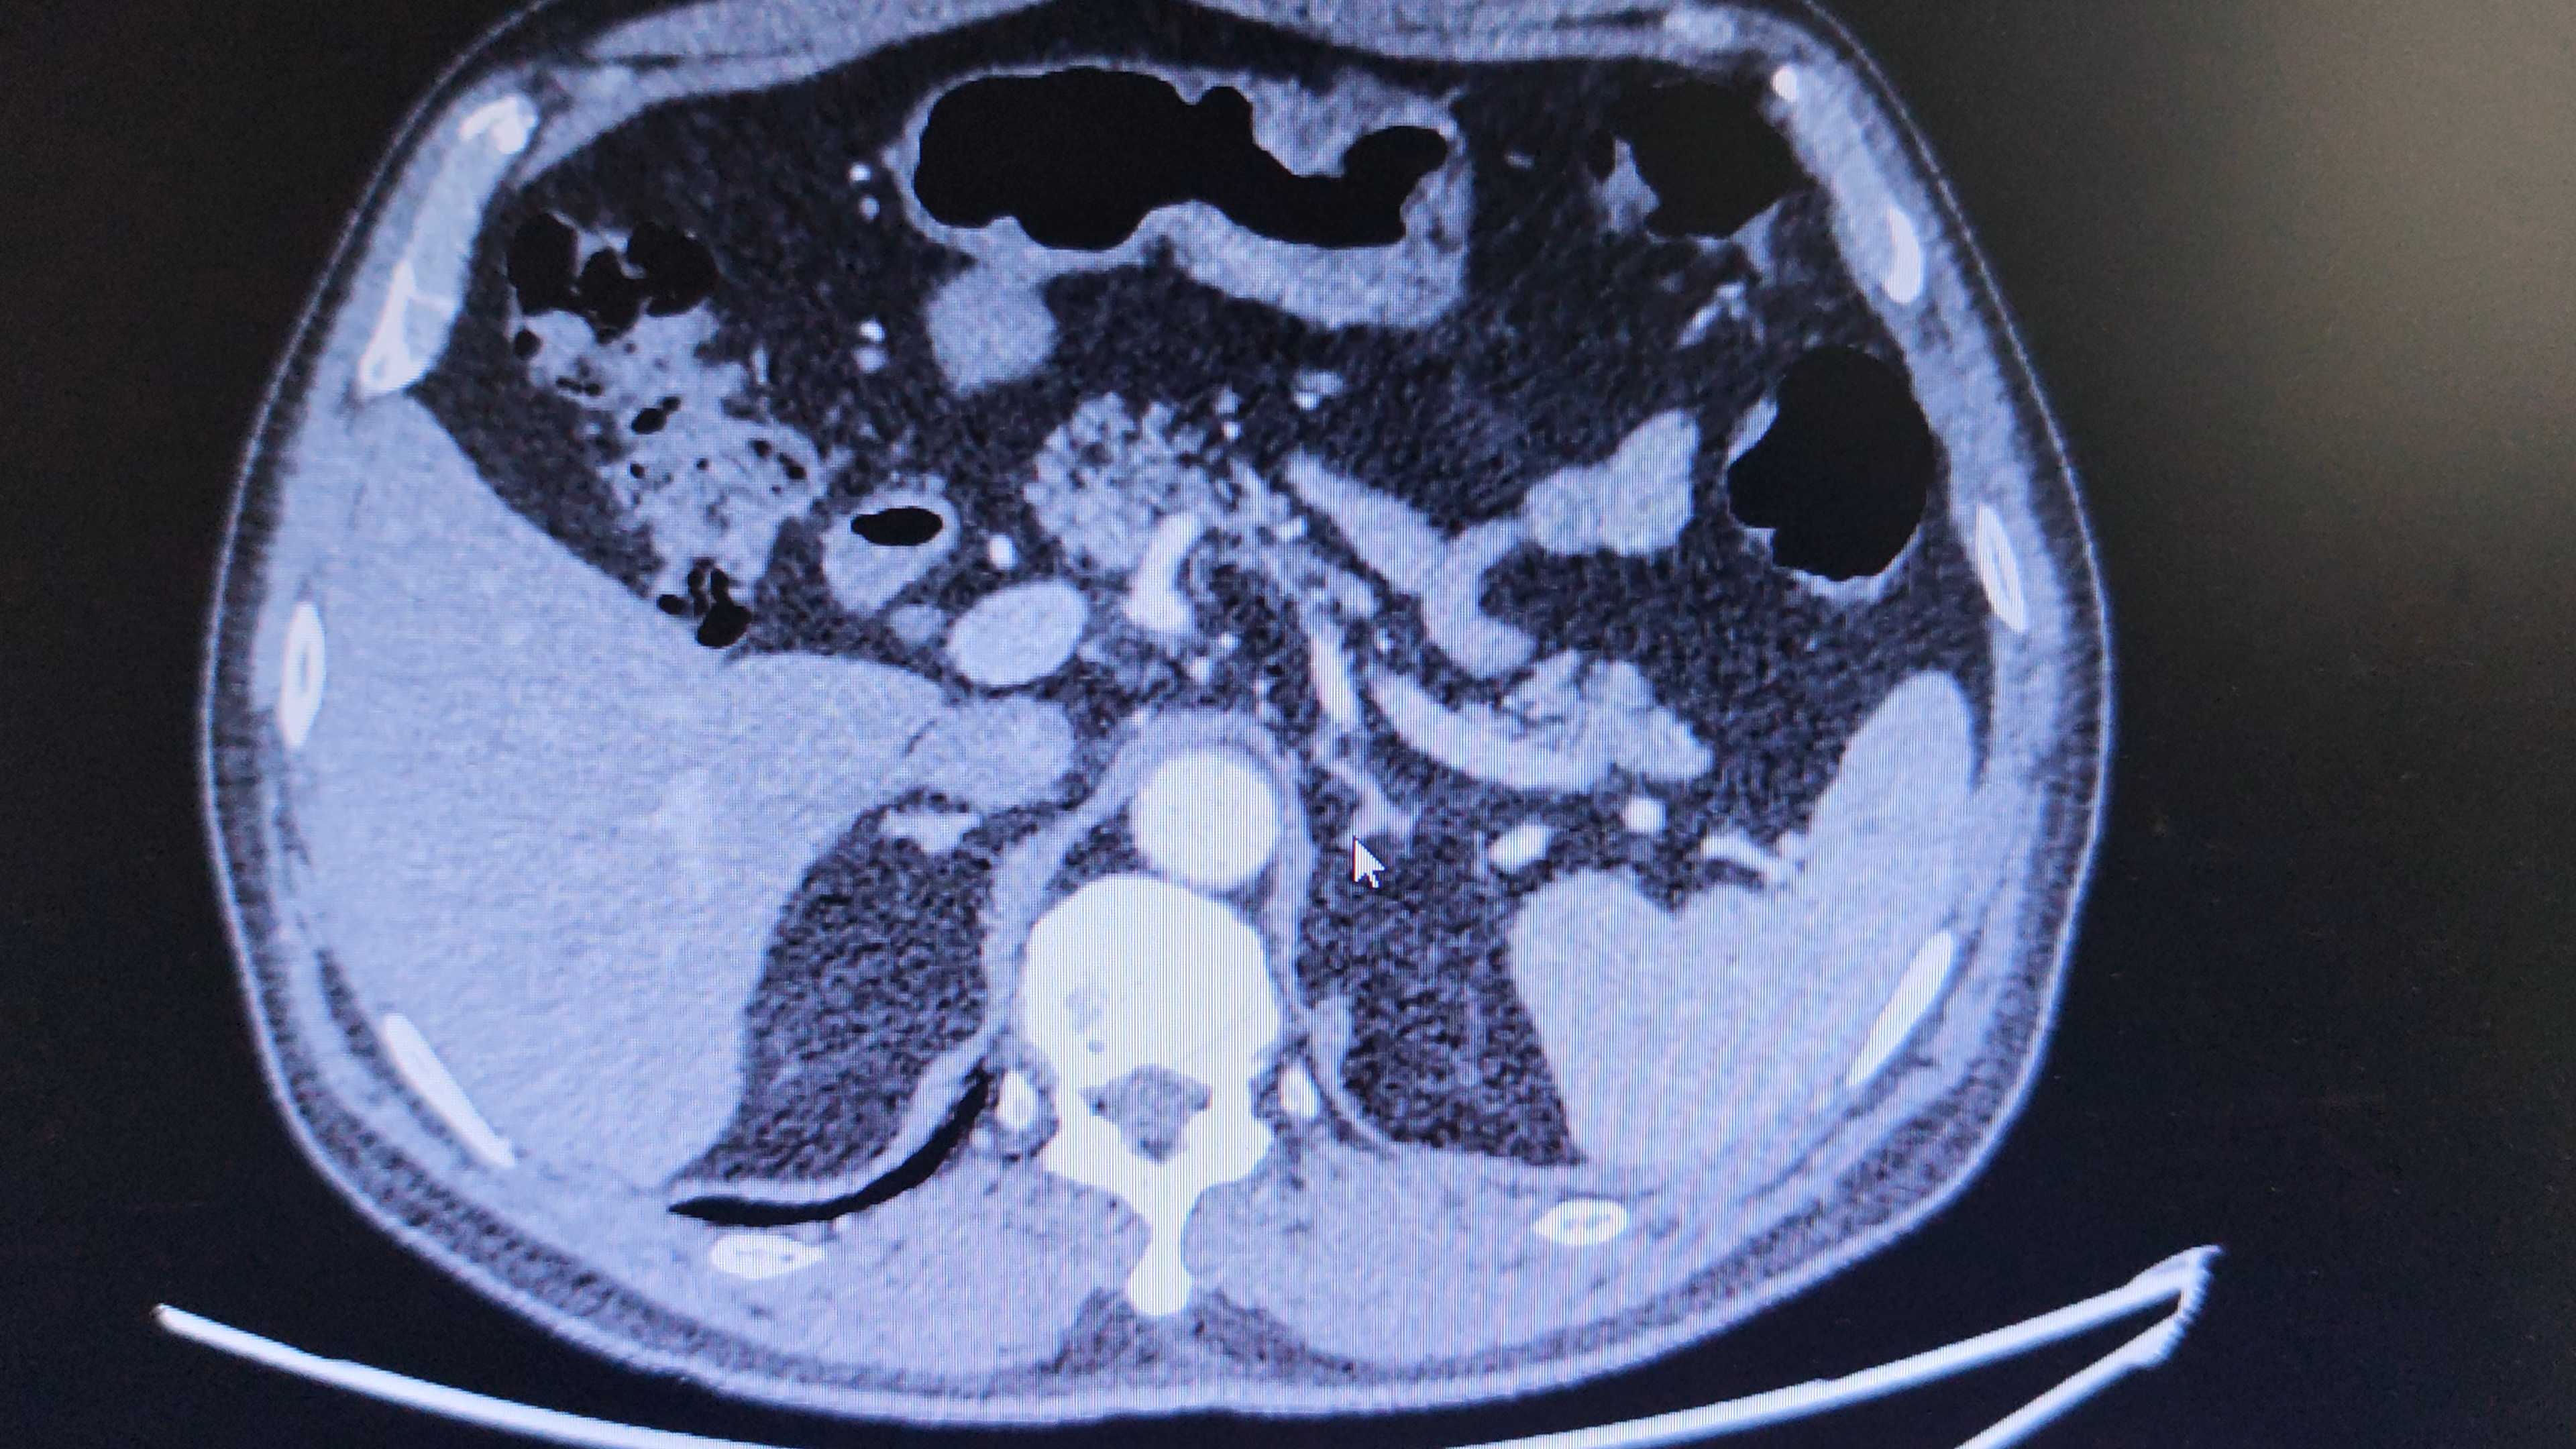

患者男,59岁,查体发现膀胱肿瘤伴肾积水3天。

CT检查提示:膀胱后壁占位,双侧肾积水。

膀胱后壁肿瘤致双侧肾积水处理方案。